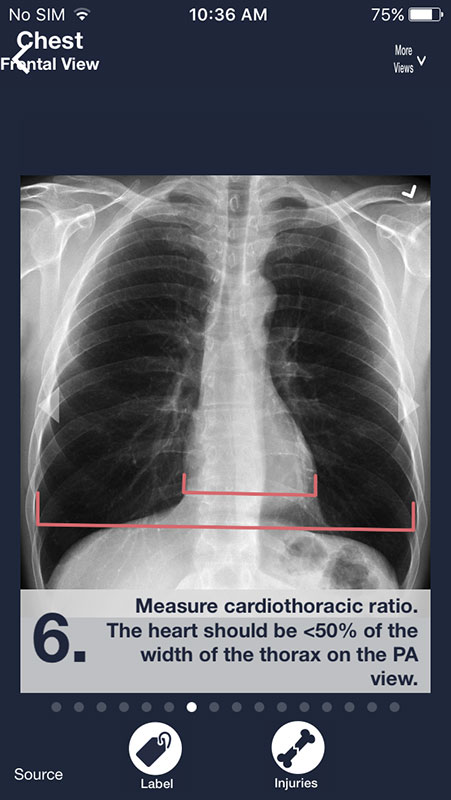

You can swipe the screen to navigate through the series of images. Each following image is annotated and contains a piece of advice on what to look for on a radiograph in order to distinguish between normal anatomy and abnormalities/pathologies.

There are two buttons below each image. First, Label button annotates the structures in the first image, showing them in different colors with names.

Most radiographs can be viewed from multiple angles. Simply tap on More Views above each image and choose between different views.

For example, you can view shoulder from AP view, apical oblique, or lateral Y, or choose to view chest X-rays from frontal or lateral view, which may be particularly useful to spot some abnormalities that might not be visible from frontal view (for example atelectasis).